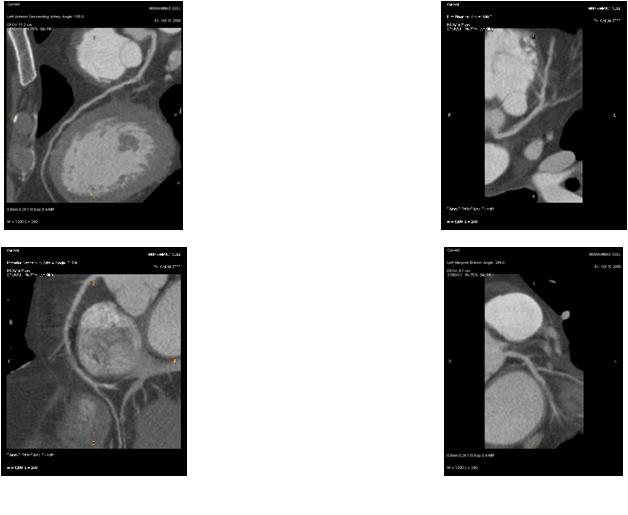

M/60 C.C. Atypical chest pain (since 2months) / Diabetes + / HR at MDCT scan: 70-75 bpm.

CHARY DURAIKANNU, VRR Diagnostics, INDIA

HIT : 82